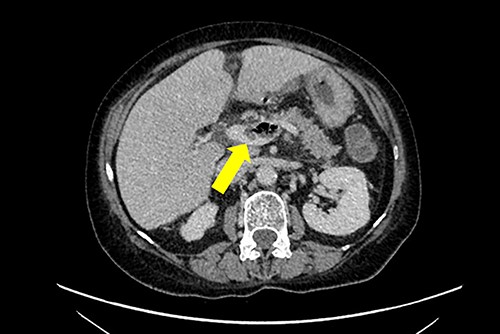

A non-contrast-enhanced computed tomography (CT) scan of the abdomen and pelvis was performed. This demonstrated acute sigmoid diverticulitis with air tracking along the course of the inferior mesenteric vein (Figs 1 and 2). Additionally, a large portal vein thrombus was seen with extension to the left intrahepatic portal vein (Fig. 3) and evidence of portal venousgas.

Axial section of a non-contrast CT scan with showing air tracking within the inferior mesenteric vein at various levels (yellow arrow).